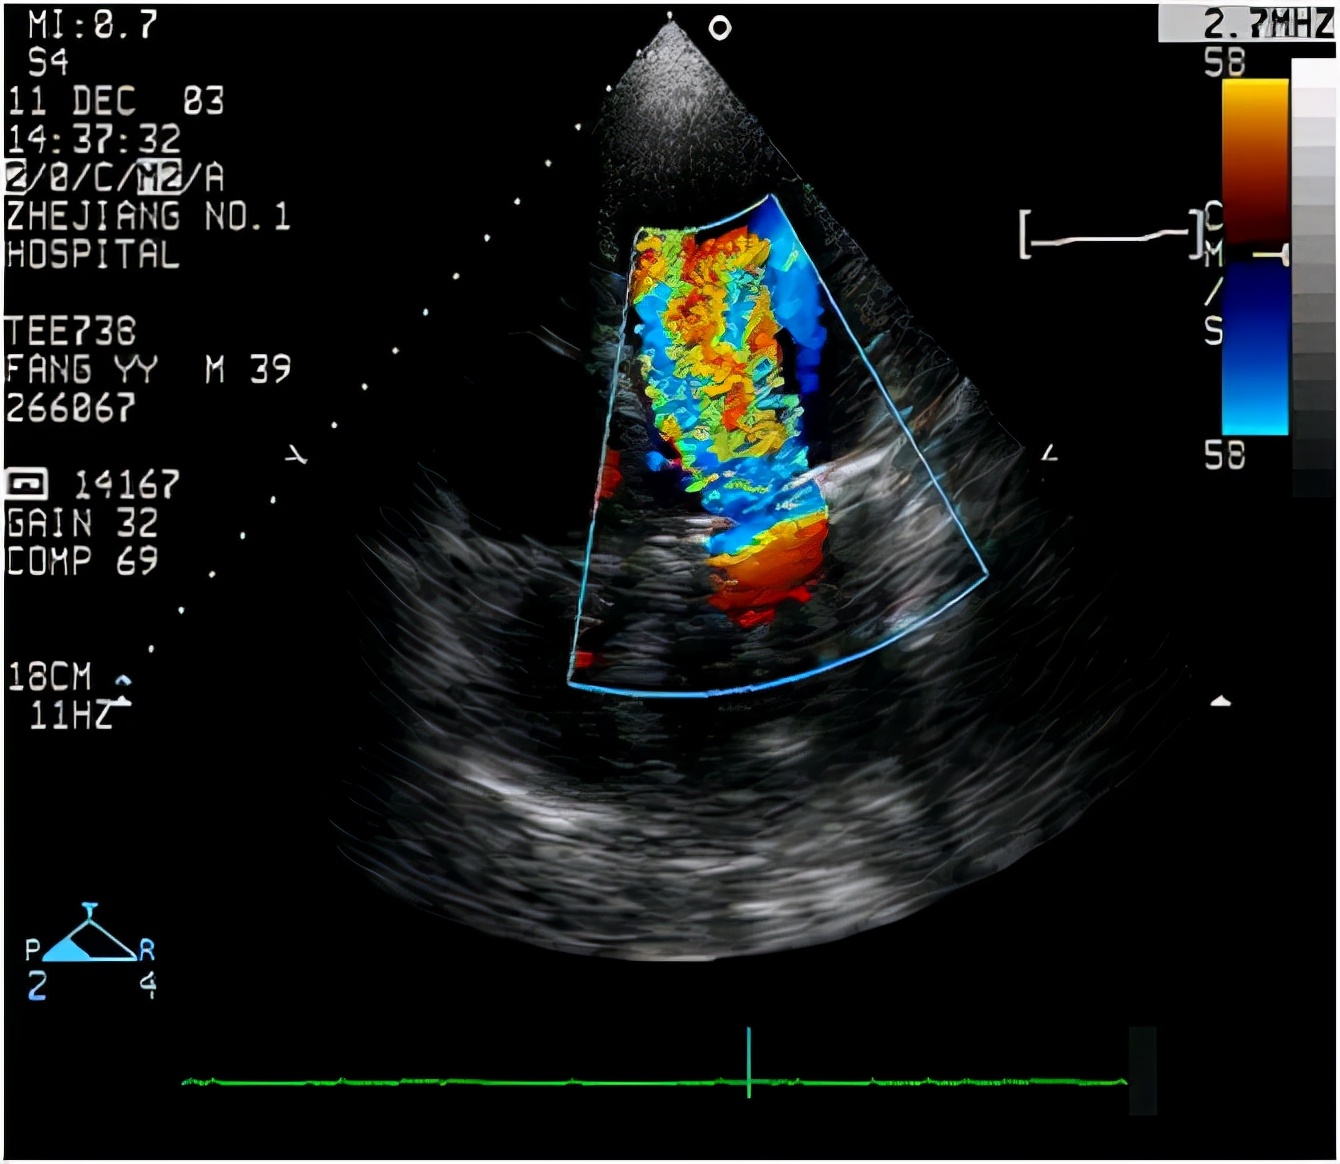

没想到心脏彩超检查时,就真的发现了问题:刘女士的右心房和右心室有不同程度的增大,房间隔中部连续性中断,缺损最大达26mm。

刘女士被确诊为房间隔缺损。而且属于缺损较为严重的等级,因为刘女士已经可以感觉到呼吸吃力,易劳累等临床表现,如果不及时手术修补治疗,很可能会导致心衰、肺淤血、心房纤颤、心房扑动等并发症,最终导致寿命缩短,发生充血性心力衰竭死亡。